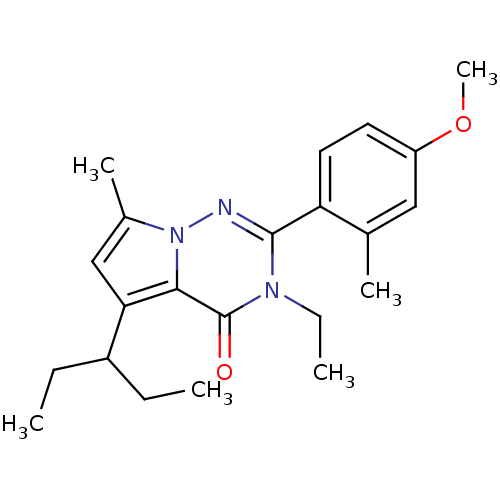

TargetCorticotropin-releasing factor receptor 1(Homo sapiens (Human))

Dupont Pharmaceuticals

Curated by ChEMBL

Dupont Pharmaceuticals

Curated by ChEMBL

Affinity DataEC50: 0.300nMAssay Description:Antagonist activity at human CRF1 receptor expressed in CHO-K1 cells assessed as CRF-stimulated cAMP accumulation by enzyme immunoassayMore data for this Ligand-Target Pair

Affinity DataEC50: 0.420nMAssay Description:Antagonist activity at CRF-R1 in mouse AtT-20 cells assessed as inhibition of human CRF induced cAMP accumulation after 30 mins by radioimmunoassayMore data for this Ligand-Target Pair

Affinity DataEC50: 0.440nMAssay Description:Antagonist activity at CRF-R1 in mouse AtT-20 cells assessed as inhibition of human CRF induced cAMP accumulation after 30 mins by radioimmunoassayMore data for this Ligand-Target Pair

Affinity DataEC50: 0.450nMAssay Description:Antagonist activity at CRF-R1 in mouse AtT-20 cells assessed as inhibition of human CRF induced cAMP accumulation after 30 mins by radioimmunoassayMore data for this Ligand-Target Pair